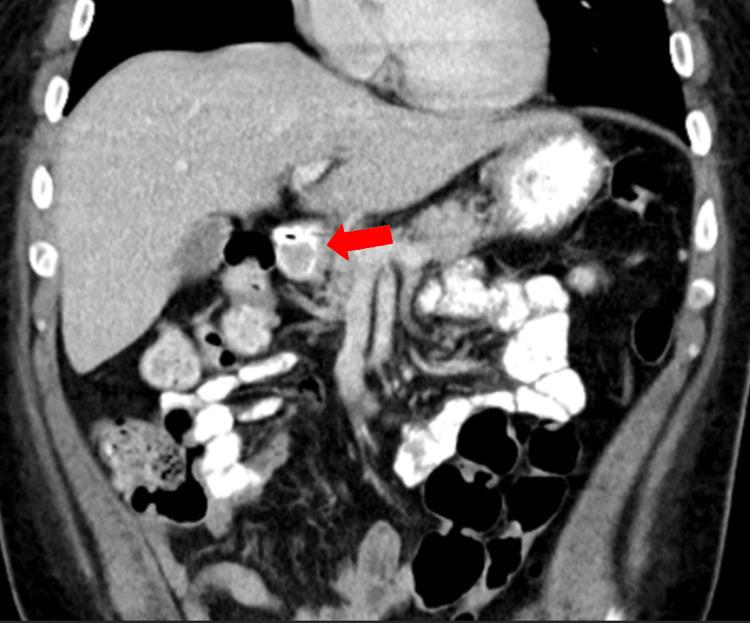

In this case report, we discuss a very rare presentation of a duodenal carcinoid tumor causing a gastric outlet obstruction that was initially misdiagnosed as gastroparesis due to uncontrolled diabetes. This tumor did not present with the usual symptoms or as carcinoid syndrome, as it was negative for all tumor markers and metanephrines. Treatment typically includes preoperative administration of somatostatin analogs, however, these were not used as the tumor showed no evidence of hormone secretion. Early operative treatment is indicated due to the poor prognosis associated with metastatic disease; however, this nonfunctioning tumor, with less than 3% Ki-67 positivity, was classified as low-grade. During esophagogastroduodenoscopy (EGD) and surgical resection, the mass was observed to be highly mobile, intermittently prolapsing retrograde through the pylorus and acting as a one-way valve, obstructing the passage of fluids and food into the duodenum. Consequently, this gastric outlet-like picture was intermittent. The patient's history of uncontrolled diabetes and gastroparesis complicated the diagnosis as each episode of vomiting resolved on its own without any interventions. This made diagnosis of his underlying condition difficult. In this case, we present this rare type of carcinoid obstruction as well as surgical options and surveillance for these tumors.

在本病例报告中,我们讨论了一例极为罕见的十二指肠类癌肿瘤表现,该肿瘤导致胃出口梗阻,最初因糖尿病控制不佳被误诊为胃轻瘫。此肿瘤未表现出常见症状或类癌综合征,因为所有肿瘤标志物和甲氧基肾上腺素均为阴性。治疗通常包括术前使用生长抑素类似物,然而,由于肿瘤未显示激素分泌证据,未使用这些药物。鉴于转移性疾病预后较差,应尽早进行手术治疗;然而,此无功能肿瘤的Ki-67阳性率低于3%,被归类为低级别。在食管胃十二指肠镜检查(EGD)和手术切除过程中,观察到肿块活动度极高,间歇性地逆行通过幽门突出,起到单向瓣膜的作用,阻碍液体和食物进入十二指肠。因此,这种类似胃出口梗阻的情况是间歇性的。患者未控制的糖尿病和胃轻瘫病史使诊断复杂化,因为每次呕吐发作均自行缓解,无需任何干预。这使得对其潜在病情的诊断变得困难。在此病例中,我们展示了这种罕见类型的类癌梗阻以及针对这些肿瘤的手术选择和监测。